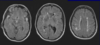

Chronic cortical ischemic stroke

Aftermonths,allthat remains is a cystic cavity surrounded by gliotic tissue with glial strands (circle)

-There is compensatory (ex- vacuo) ventricular enlargement (open arrow)

Wallerian degeneration of the cerebral peduncle and corticospinal tract in the pons. (arrows)